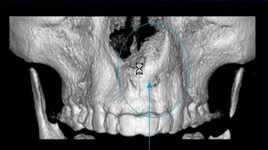

3D DVT - NewTom

Je speciální zubní digitální tříprostorový tomograf (3D), který umožňuje na základě jediného

snímkování vytvořit všechny typy RTG zobrazení, které jsou pro lékaře potřebné. Díky používané technologii tzv. „kuželového paprsku“ a speciálním senzorům je

výrazně zmenšená dávka záření - o více jak 80% proti klasickému CT vyšetření. To je významné zejména u dětí. Pomocí tohoto přístroje je možné zjisti skutečnou situaci v čelistních kostech pacienta tedy množství kosti - můžeme změřit skutečnou šířku i výšku kosti, i kvalitu kosti (hustotu) v místě uvažované implantace. 3D (tříprostorové) zobrazení umožňuje zvýšit prostorovou představu operatéra ještě před vlastní operací a zároveň pacientovi lépe objasnit a ukázat oblast plánovaného zavedení implantátu.

Pacient „neumí číst“ RTG snímky, ale díky 3D zobrazení vidí „svoji skutečnou čelist“

- např. jak je nízká či úzká, vidí průběh nervu nebo velikost čelistní dutiny, což mu umožní i pochopení nutnosti v některých případech provést pomocné zákroky ještě před vlastním zavedením implantátu (viz. kostní štěp, sinus lift, kostní granulát...).

Vyšetření pomocí tohoto přístroje používáme i ve stomatochirurgii (zlomeniny čelistí, zuby moudrosti, cysty, onemocnění čelistního kloubu), ortodoncii (retinované zuby, nadpočetné zuby), parodontologii atd.